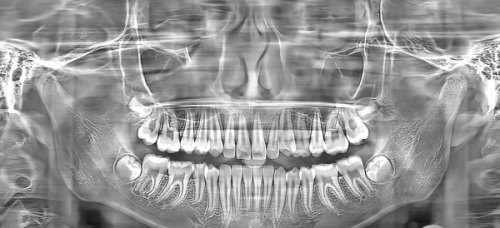

舌侧矫正(上舌下唇)是一种精细兼顾美观与矫正成效的正畸方案,简单来说就是在上门牙的舌侧(牙齿内侧)安装定制矫正托槽,下牙则根据口腔情况搭配适配的矫正方式,既理想隐藏了前牙区的矫正装置,满足极致美观需求,又能保护全口牙齿咬合关系的调整与矫正成效的稳定性。

舌侧矫正(上舌下唇)和唇侧矫正更直观的区别在于托槽安装位置:舌侧矫正的托槽安装在上门牙的内侧(舌侧),从外部完全看不到任何矫正装置,理想满足了对美观有极高要求的人群需求,比如职场人士、学生、艺人等;而唇侧矫正的托槽安装在牙齿外侧,一眼就能看到,美观性相对较弱,适合对美观要求不高的人群。

舌侧矫正是否可以只矫正上门牙,需要根据个人的口腔实际情况来判断,不能一概而论。如果只是上门牙存在轻微的排列不齐,上下牙咬合关系正常,下牙及其他牙齿没有明显畸形,经过专精正畸医生的全方面评估后,是可以考虑单矫上门牙的。

但需要明确的是,单矫上门牙的适用范围比较窄,多数情况下,牙齿畸形往往伴随着咬合关系的异常,全口矫正才能更好地调整上下牙的咬合平衡,保护矫正后的牙齿稳定性与长期口腔健康。比如宜宾口腔机构的陈琛医生,会为患者进行一对一的口腔检查、数字化扫描与评估,根据牙齿畸形程度、咬合情况、面型等多方面因素,给出更科学、更适合的矫正方案,无论是单矫还是全口矫正,都会确保方案的合理性与有效性。